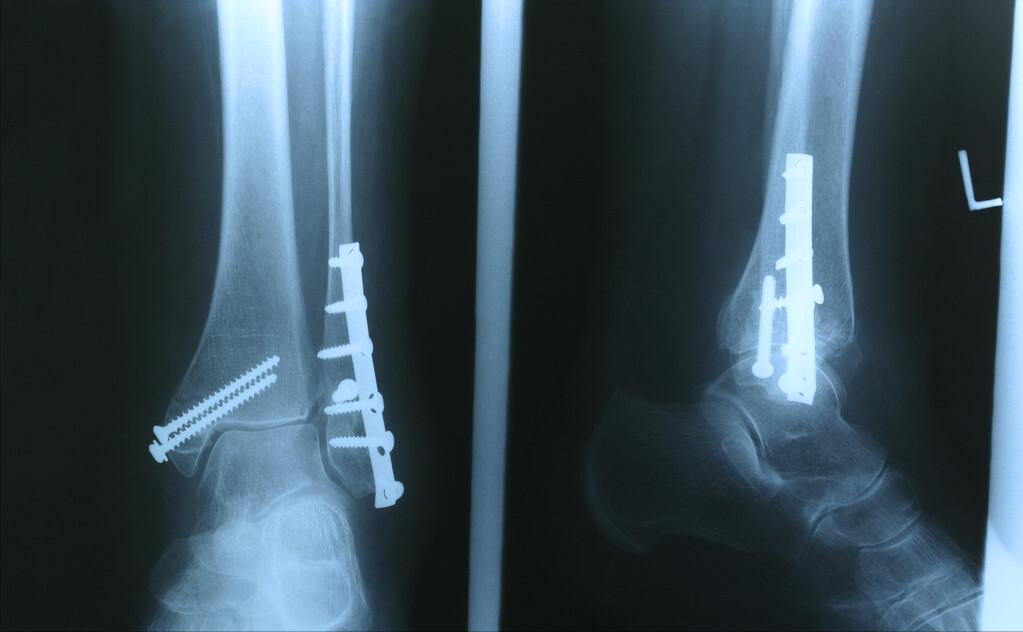

5.内固定

内固定也就是我们常说的打钢板,把骨折周围的组织切开,在骨骼表面钉上钢板,来固定骨折端,不至于过度活动。